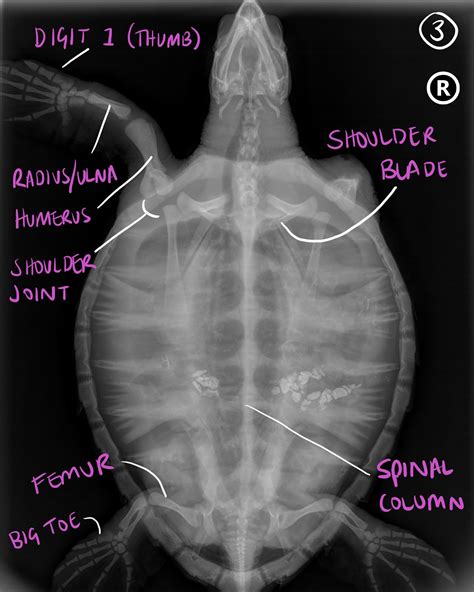

Dorsoventral (DV) View

For the dorsoventral (DV) view, the turtle is placed on its back , with the beam entering through the dorsal (top) surface and exiting through the ventral (bottom) surface. The goal is to get a clear, symmetrical image of the turtle’s internal organs and skeletal structures. Start by gently positioning the turtle in dorsal recumbency, ensuring that the spine is straight and aligned with the center of the X-ray beam. Use foam wedges or sandbags to support the turtle and prevent it from rolling. Take care to avoid excessive pressure on the turtle’s limbs or neck. Collimate the beam to include the entire shell and ensure that the central ray is centered over the mid-carapace. This view is particularly useful for assessing lung fields, liver size, and the presence of any abdominal masses or foreign bodies.